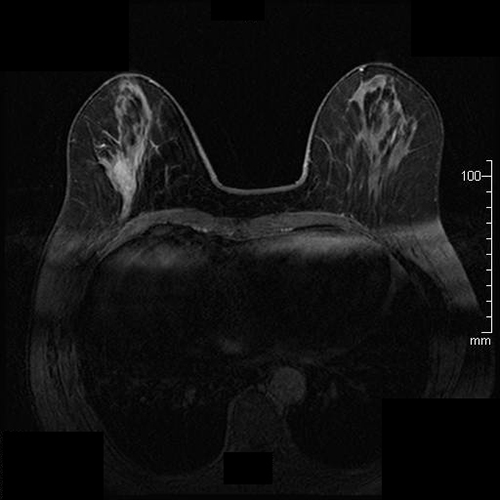

乳房MRIの最新技術と応用に関する詳細な情報を提供する専門書。- タイトル: Breast MRI: State of the Art and Future Directions- 巻号: Volume 5- 編集者: Kaya P. Pincus, Ritesh Mann, Savannah Partridge- 出版社: Academic Press- 内容: 乳房MRIの最新技術と応用に関する情報- キーフィーチャー: 乳房MRIの技術、解釈、最新の研究成果に関する情報ご覧いただきありがとうございます。